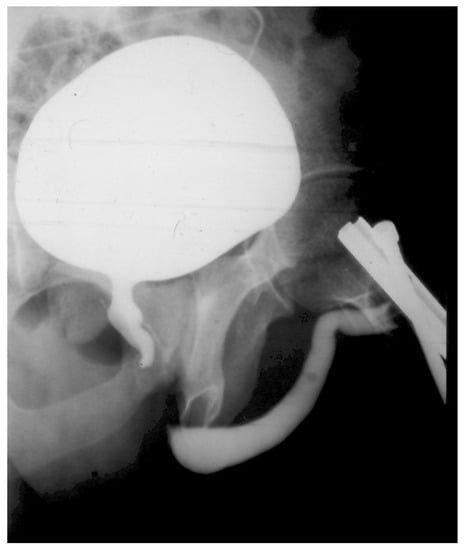

Prior to surgery, a physical examination along with a retrograde and voiding cystography was performed (Figure 5). Patients with no bladder catheter also underwent flowmetry. All patients underwent deferred perineal urethroplasty, and some required a combined approach. All but three were anastomotic urethroplasties. Surgical data was collected, including the use of an auxiliary maneuver as described previously to achieve a tension-free anastomosis.

Figure 5. Cystourethrography in a patient with urethral disruption.